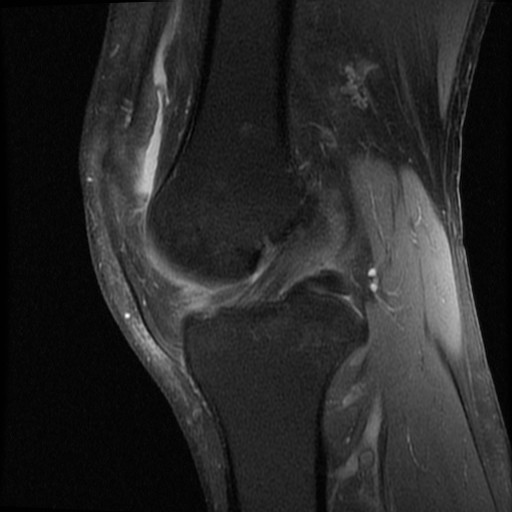

Mann i 30 årene. Vridningstraume 4 måneder siden; “ikke blitt bra ennå”, ønsket MR kne.

Diagnose: Bøttehank ruptur av fremre del av mediale menisk, såklat “double ACL sign”.

Sees også tydelig på coronale og axiale bilder (bilde 2 og 3):